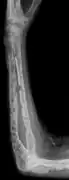

Medical imaging

The diagnostic examination of a person with suspected multiple myeloma typically includes a skeletal survey. This is a series of X-rays of the skull, axial skeleton, and proximal long bones. Myeloma activity sometimes appears as "lytic lesions" (with local disappearance of normal bone due to resorption). And on the skull X-ray as "punched-out lesions" (pepper-pot skull). Lesions may also be sclerotic, which is seen as radiodense.[47] Overall, the radiodensity of myeloma is between −30 and 120 Hounsfield units (HU).[48] Magnetic resonance imaging is more sensitive than simple X-rays in the detection of lytic lesions, and may supersede a skeletal survey, especially when vertebral disease is suspected. Occasionally, a CT scan is performed to measure the size of soft-tissue plasmacytomas. Bone scans are typically not of any additional value in the workup of people with myeloma (no new bone formation; lytic lesions not well visualized on bone scan).